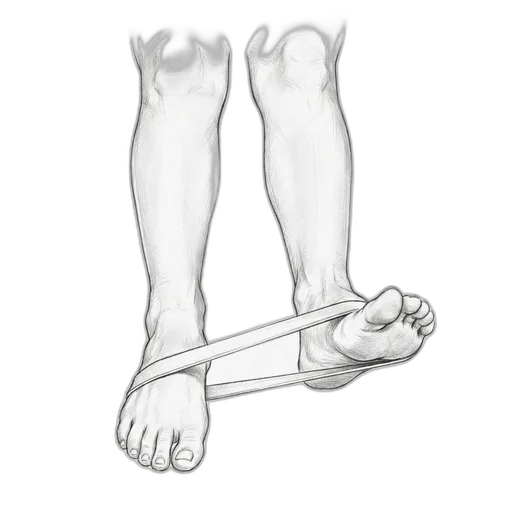

Resistance Band Eversion

This exercise strengthens the peroneal muscles — the muscles on the outside of your lower leg that prevent your ankle from rolling inward. Think of them as your ankle's natural brace. After a sprain, these muscles often weaken and their reflexes slow down, which is a big reason why people re-sprain the same ankle. Resistance band training rebuilds that strength and re-trains the "catch reflex" that protects you.

What to expect: By 4–6 weeks, your ankle should feel noticeably more stable during walking and on uneven surfaces. Strength testing typically shows meaningful improvement by 6 weeks. The real win: a significantly lower chance of re-spraining your ankle — studies show up to 50% reduction in re-injury with consistent peroneal training.

How to do it: Sit with your legs out in front of you. Loop a resistance band around the ball of your foot and anchor the other end to something sturdy (a table leg works well) or your other foot. Slowly turn the sole of your foot outward against the band's resistance, then return slowly. Keep your knee still — the movement should come from your ankle, not your leg.